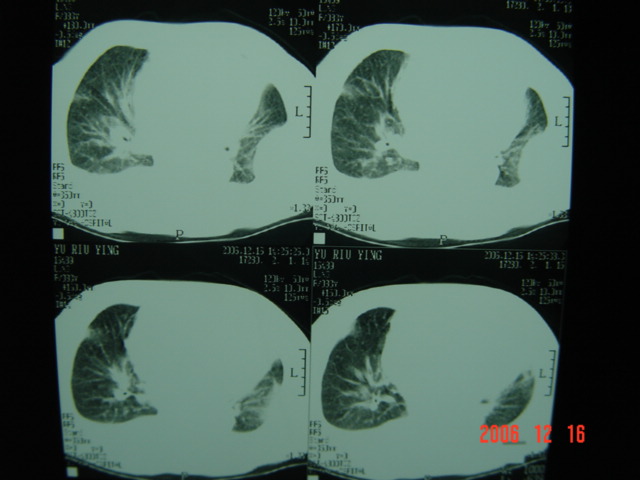

标题: CT5663:女、83岁,轻微咳嗽、左下胸痛。 [打印本页]

标题: CT5663:女、83岁,轻微咳嗽、左下胸痛。

左第八肋腋侧呈膨胀性骨质破坏,内侧见软组织密度肿块。左肺舌段呈楔形实变,基底近胸壁,尖端向肺门。双侧胸壁后缘见新月形水样密度区。

考虑:1、左第8肋骨转移瘤;

2、左肺舌叶肺栓塞可能性大;

3、双侧中量胸腔积液。